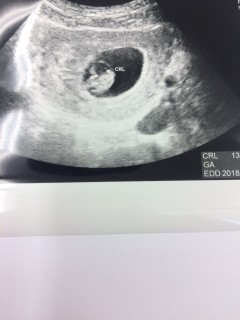

無事に胎芽・心拍を確認できました!

前回の5w5dでは胎嚢と卵黄嚢のみでしたが、2週間でしっかりと赤ちゃんが見えて感動しました!

胎芽13.4mm!

前回の妊娠は胎嚢確認後の流産だったので、まだまだ不安は大きいですが一歩先に進めてホッとしています。